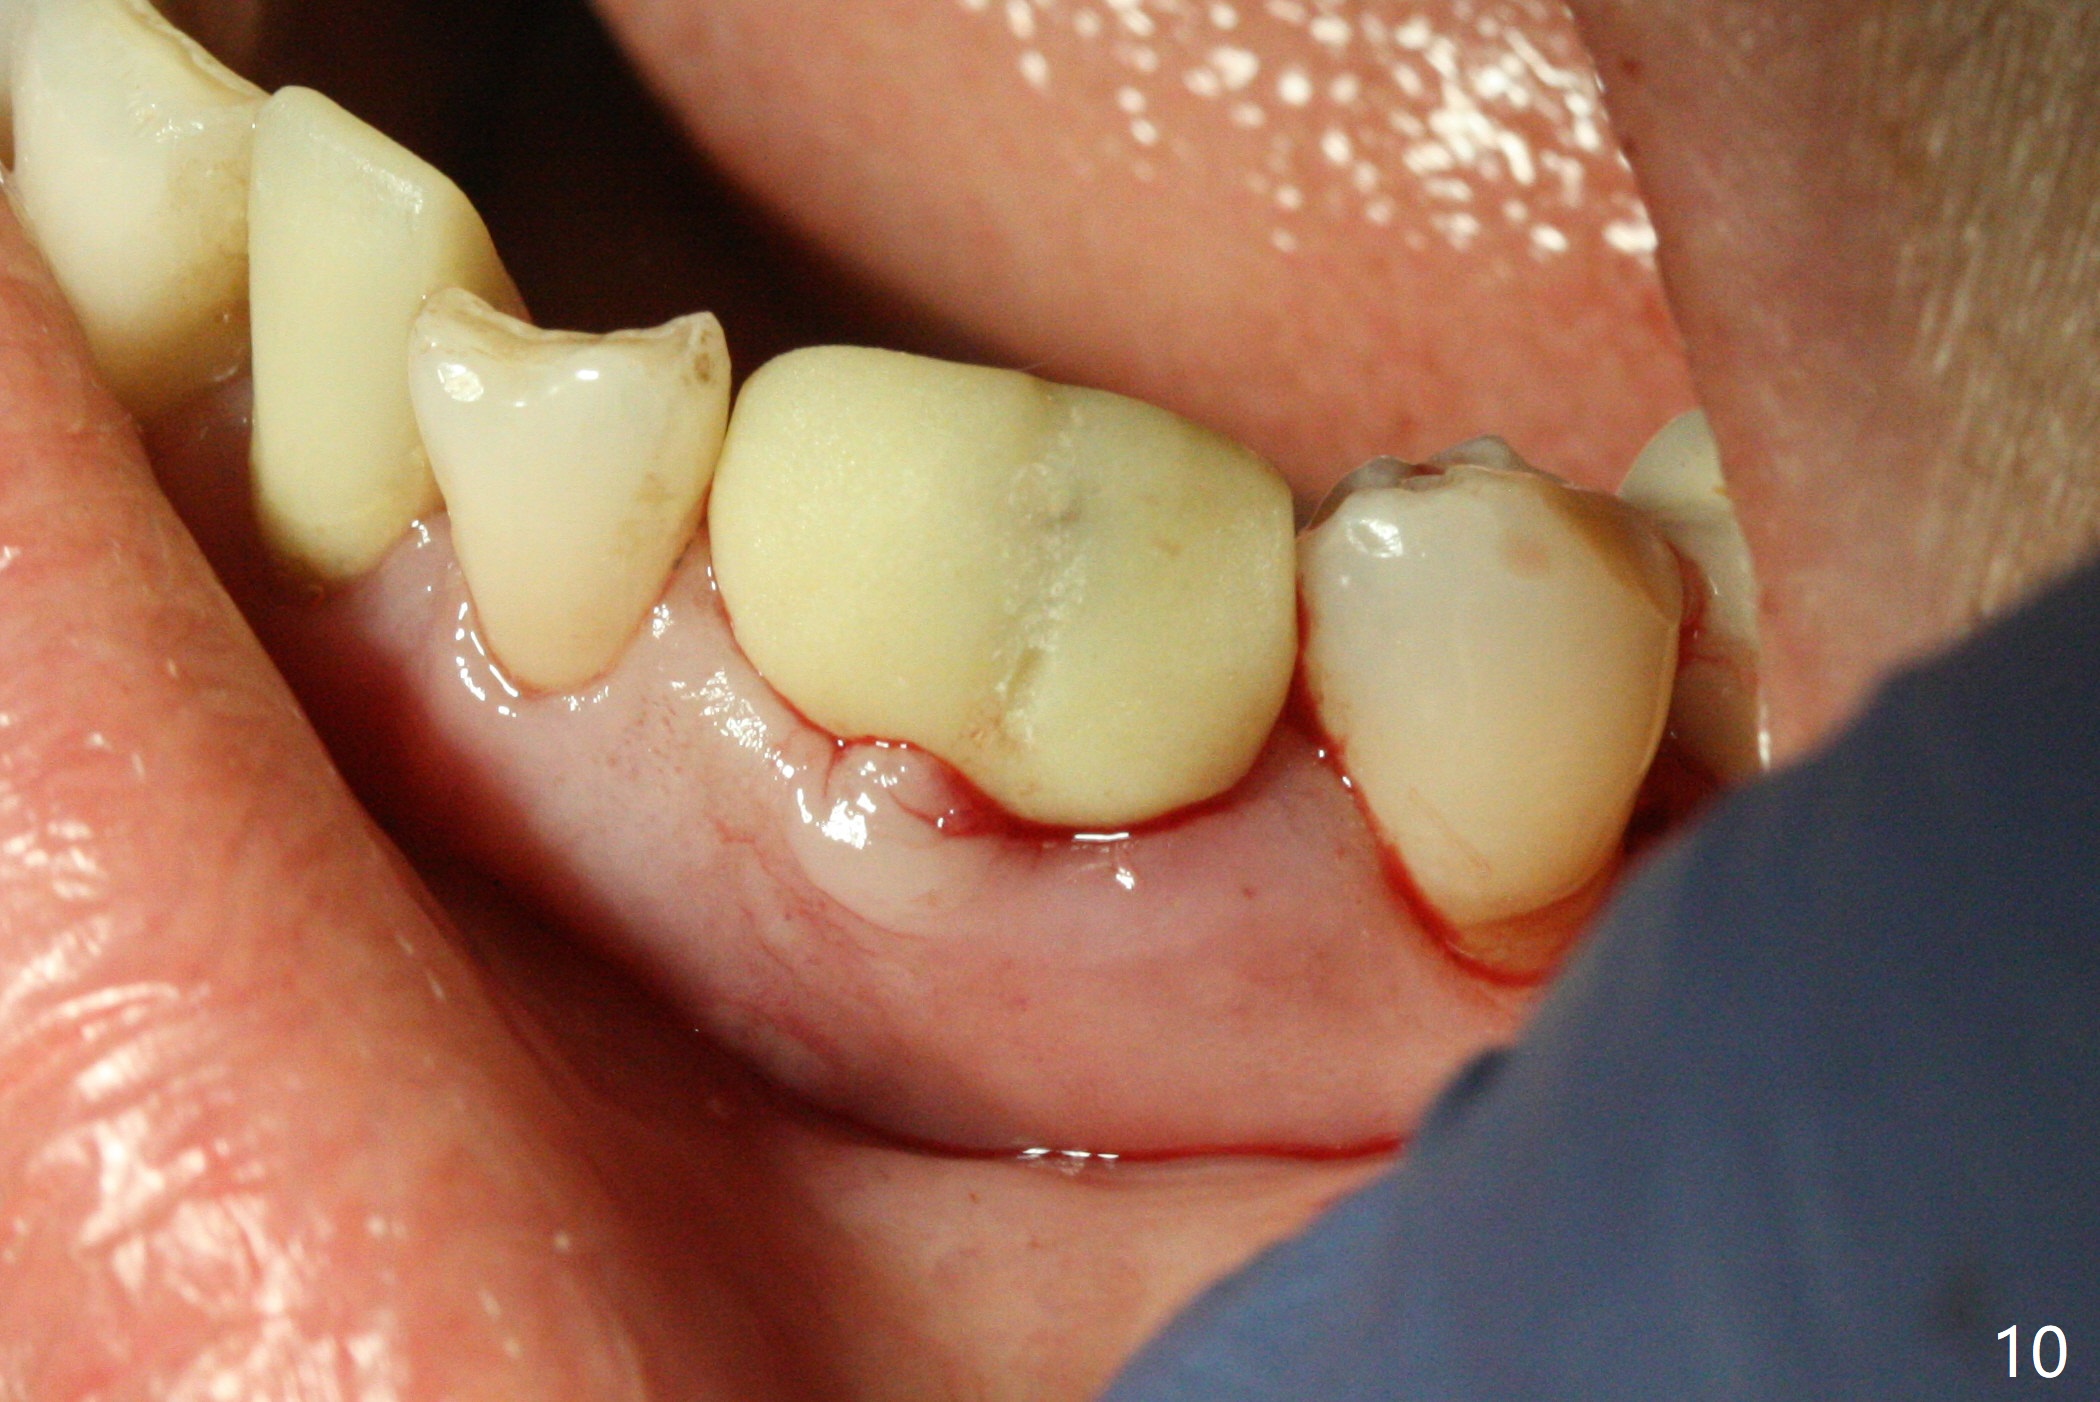

There is a fistula buccal to the apex of the tooth #23 preoperatively (Fig.1), which is related to loss of the buccal plate of the socket of #23. Therefore an implant is placed mainly in the socket of #22 (Fig.3). The lingual (Fig.2 L) gingiva appears to have more extensive inflammation. After extraction, the lingual (Fig.3 L) gingival margin is significantly lower than the buccal one. The lingual crest is ~ 4 mm lower than the buccal one. A 3.8x10 mm dummy implant is placed tentatively with an apical space (Fig.4). When a same dimension definitive implant is placed with 40 Ncm, it is 2 mm below the lingual gingival margin, whereas 6-7 mm below the buccal one (Fig.5). Vanilla graft is placed before placement of a 5.5x4(5) mm abutment (Fig.6,7). There is a 2-3 mm lingual (L) gap to be filled with the allograft secondarily to prevent periimplantitis (Fig.7). Later the abutment is changed to a longer and smaller one (Fig.8) with more of the allograft (*). After trimming of the abutment (Fig.9 (*: papilla between the fused teeth)), an immediate provisional is fabricated to close the socket (Fig.10, similar to Fig.1). The majority of the bone graft seems to be in place 8 months postop (Fig.12). The implant appears to have been placed buccal, consistent with the thin and slightly erythematous buccal gingiva (Fig.13). The ridge completely regenerates 2 years post cementation (Fig.14).